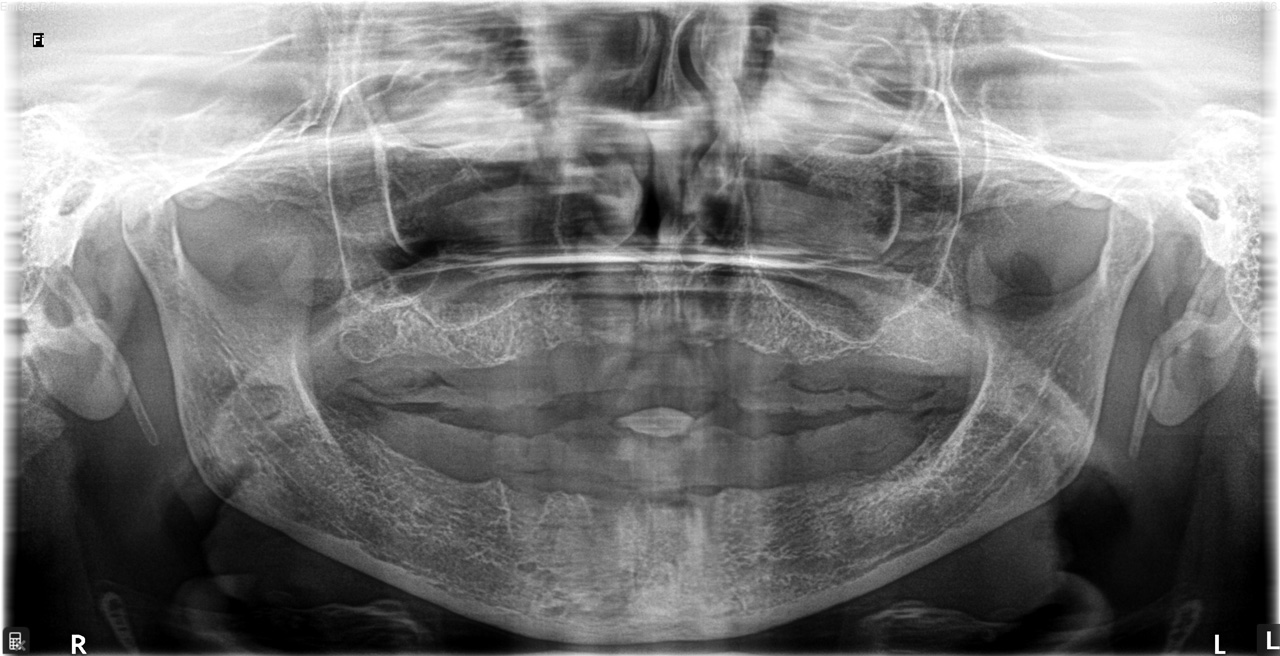

Teljes fogatlanság helyreállítása 2 nap alatt

Teljes fogatlanság helyreállítása 2 nap alatt azonnal terhelhető svájci IHDE implantátumokkal és PMMA műanyag hidakkal. Intraorális szkennerrel vettünk lenyomatot az implantáció után, és erre a digitális mintára készítette el a fogtechnika a hidak digitális tervezését, majd faragta ki műanyagból. Ezt a gyors munkát az azonnal terhelhető implantátumok és a digitális lenyomat, tervezés segítségével tudtuk megcsinálni mindössze 2 nap alatt. Dr. Kelemen Péter és a Symbion Fogtechnika munkája.